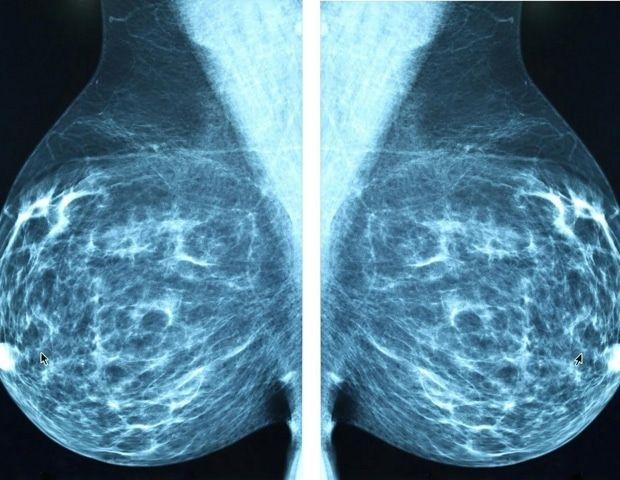

Oct 14 2025 An innovative biotech startup founded by researchers at Washington University School of Medicine in St. Louis has been acquired by Lunit, a leading company in developing AI-based technologies for cancer prevention and early detection. The WashU startup, Prognosia, was created to develop software that harnesses AI to analyze mammograms and more accurately predict a woman's five-year risk of developing breast cancer. The startup's first software package, Prognosia Breast, received Breakthrough Device Designation from the Food and Drug Administration (FDA) earlier this year, putting it on a fast track to full market approval. Lunit's acquisition of Prognosia can help accelerate the final steps of the process to bring the technology into the clinic. Prognosia was co-founded by Graham A. Colditz, MD, DrPH, the Niess-Gain Professor of Surgery at WashU Medicine and associate director of prevention and control at Siteman Cancer Center, based at Barnes-Jewish Hospital and WashU Medicine; and Shu (Joy) Jiang, PhD, an associate professor of surgery in the Division of Public Health Sciences in the Department of Surgery at WashU Medicine. "We are excited to work with Lunit to bring this technology to the clinic," Jiang said. "Lunit already has the infrastructure in place to streamline production and clinical implementation of our software that would be extraordinarily difficult for a new startup to build from scratch. Integrating our software into their existing systems could help this new technology get into the hands of physicians and patients very quickly." The system produces a five-year breast cancer risk score that makes it possible to compare a woman's personalized risk to an average risk based on national breast cancer incidence rates. This provides a meaningful estimate that is aligned with the U.S. national risk reduction guidelines, so that clinicians will know what options to discuss if a patient's breast cancer risk is elevated. "Improved risk prediction can help early detection, which has the potential to increase the likelihood of successful treatment that is less disruptive to people's lives," said Colditz, an internationally renowned cancer prevention researcher who has led the field for decades. "We recognized that there is a tremendous wealth of information about breast cancer development already stored and continuing to be newly collected in the form of regular mammograms. Until recently, there was no way to use this information to inform risk prediction or to develop new and better prevention strategies." Improving accuracy Past research led by Colditz and Jiang has shown their system is more than twice as accurate as the standard method of identifying individuals at high risk of developing breast cancer over the next five years. The standard method is based on questionnaires that include factors such as age, race and family history of breast cancer. Research also has shown that the technology maintains its high performance across multiple demographic groups, including among people of diverse races, ages and differing breast densities. These results led to the technology's recent FDA Breakthrough Device designation, which provides an accelerated review process for full market approval with the goal of giving patients and clinicians access to promising new medical devices sooner. The designation recognizes that the software already has undergone rigorous testing and has shown excellent promise in its potential to improve clinical care. The developers said the technology could be easily integrated into existing clinical workflows and is compatible with both types of mammogram imaging available: the four 2D views of the breast produced by full-field digital mammography and the synthetic 3D view of the breast produced by digital breast tomosynthesis. A roadmap for growth Colditz and Jiang worked with WashU's Office of Technology Management (OTM) to found their AI-based biotech startup. Prognosia is a superb example of harnessing all the resources available to WashU faculty to accelerate the launch of a company. Dr. Colditz and Dr. Jiang were proactive in adapting and learning through the resources and guidance of WashU's OTM and the entrepreneurship ecosystem of St. Louis. Through Lunit's acquisition of Prognosia, we're excited to see this powerful startup venture become even better positioned to make transformative improvements in breast cancer risk estimation, prevention and early detection." Nichole R. Mercier, PhD, assistant vice chancellor and managing director of OTM Colditz and Jiang said Prognosia would not have been possible without OTM's GAP funding program, which allowed them to do the work required for the FDA's Breakthrough Device designation, as well as support from BioGenerator Ventures, which provided both financial support and expertise in business strategy from Entrepreneur-in-Residence David Smoller, PhD. "With the guidance of OTM and David Smoller, we broadened our perspective beyond the technical aspects of the software to focus on the needs of the health-care providers who will use it to care for patients," Colditz said. "That shift in mindset has been crucial to developing a technology that's truly useful in the clinical setting." Colditz and Jiang will hold advisory roles at Lunit during the pre-market review process that precedes full FDA approval of the technology and for ongoing development projects. The regulatory plan includes an initial submission for the static model of risk prediction based on mammograms taken at a single timepoint, with a roadmap to expand functionality of the software by analyzing mammograms from the same person taken at multiple timepoints to improve the accuracy of the prediction. WashU Medicine

Newswise -- An innovative biotech startup founded by researchers at Washington University School of Medicine in St. Louis has been acquired by Lunit, a leading company in developing AI-based technologies for cancer prevention and early detection. The WashU startup, Prognosia, was created to develop software that harnesses AI to analyze mammograms and more accurately predict a woman's five-year risk of developing breast cancer. The startup's first software package, Prognosia Breast, received Breakthrough Device Designation from the Food and Drug Administration (FDA) earlier this year, putting it on a fast track to full market approval. Lunit's acquisition of Prognosia can help accelerate the final steps of the process to bring the technology into the clinic. Prognosia was co-founded by Graham A. Colditz, MD, DrPH, the Niess-Gain Professor of Surgery at WashU Medicine and associate director of prevention and control at Siteman Cancer Center, based at Barnes-Jewish Hospital and WashU Medicine; and Shu (Joy) Jiang, PhD, an associate professor of surgery in the Division of Public Health Sciences in the Department of Surgery at WashU Medicine. "We are excited to work with Lunit to bring this technology to the clinic," Jiang said. "Lunit already has the infrastructure in place to streamline production and clinical implementation of our software that would be extraordinarily difficult for a new startup to build from scratch. Integrating our software into their existing systems could help this new technology get into the hands of physicians and patients very quickly." The system produces a five-year breast cancer risk score that makes it possible to compare a woman's personalized risk to an average risk based on national breast cancer incidence rates. This provides a meaningful estimate that is aligned with the U.S. national risk reduction guidelines, so that clinicians will know what options to discuss if a patient's breast cancer risk is elevated. "Improved risk prediction can help early detection, which has the potential to increase the likelihood of successful treatment that is less disruptive to people's lives," said Colditz, an internationally renowned cancer prevention researcher who has led the field for decades. "We recognized that there is a tremendous wealth of information about breast cancer development already stored and continuing to be newly collected in the form of regular mammograms. Until recently, there was no way to use this information to inform risk prediction or to develop new and better prevention strategies." Past research led by Colditz and Jiang has shown their system is more than twice as accurate as the standard method of identifying individuals at high risk of developing breast cancer over the next five years. The standard method is based on questionnaires that include factors such as age, race and family history of breast cancer. Research also has shown that the technology maintains its high performance across multiple demographic groups, including among people of diverse races, ages and differing breast densities. These results led to the technology's recent FDA Breakthrough Device designation, which provides an accelerated review process for full market approval with the goal of giving patients and clinicians access to promising new medical devices sooner. The designation recognizes that the software already has undergone rigorous testing and has shown excellent promise in its potential to improve clinical care. The developers said the technology could be easily integrated into existing clinical workflows and is compatible with both types of mammogram imaging available: the four 2D views of the breast produced by full-field digital mammography and the synthetic 3D view of the breast produced by digital breast tomosynthesis. Colditz and Jiang worked with WashU's Office of Technology Management (OTM) to found their AI-based biotech startup. "Prognosia is a superb example of harnessing all the resources available to WashU faculty to accelerate the launch of a company," said Nichole R. Mercier, PhD, assistant vice chancellor and managing director of OTM. "Dr. Colditz and Dr. Jiang were proactive in adapting and learning through the resources and guidance of WashU's OTM and the entrepreneurship ecosystem of St. Louis. Through Lunit's acquisition of Prognosia, we're excited to see this powerful startup venture become even better positioned to make transformative improvements in breast cancer risk estimation, prevention and early detection." Colditz and Jiang said Prognosia would not have been possible without OTM's GAP funding program, which allowed them to do the work required for the FDA's Breakthrough Device designation, as well as support from BioGenerator Ventures, which provided both financial support and expertise in business strategy from Entrepreneur-in-Residence David Smoller, PhD. "With the guidance of OTM and David Smoller, we broadened our perspective beyond the technical aspects of the software to focus on the needs of the health-care providers who will use it to care for patients," Colditz said. "That shift in mindset has been crucial to developing a technology that's truly useful in the clinical setting." Colditz and Jiang will hold advisory roles at Lunit during the pre-market review process that precedes full FDA approval of the technology and for ongoing development projects. The regulatory plan includes an initial submission for the static model of risk prediction based on mammograms taken at a single timepoint, with a roadmap to expand functionality of the software by analyzing mammograms from the same person taken at multiple timepoints to improve the accuracy of the prediction. About WashU Medicine WashU Medicine is a global leader in academic medicine, including biomedical research, patient care and educational programs with more than 3,000 faculty. Its National Institutes of Health (NIH) research funding portfolio is the second largest among U.S. medical schools and has grown 83% since 2016. Together with institutional investment, WashU Medicine commits well over $1 billion annually to basic and clinical research innovation and training. Its faculty practice is consistently among the top five in the country, with more than 2,000 faculty physicians practicing at 130 locations. WashU Medicine physicians exclusively staff Barnes-Jewish and St. Louis Children's hospitals -- the academic hospitals of BJC HealthCare -- and Siteman Cancer Center, a partnership between BJC HealthCare and WashU Medicine and the only National Cancer Institute-designated comprehensive cancer center in Missouri. WashU Medicine physicians also treat patients at BJC's community hospitals in our region. With a storied history in MD/PhD training, WashU Medicine recently dedicated $100 million to scholarships and curriculum renewal for its medical students, and is home to top-notch training programs in every medical subspecialty as well as physical therapy, occupational therapy, and audiology and communications sciences.